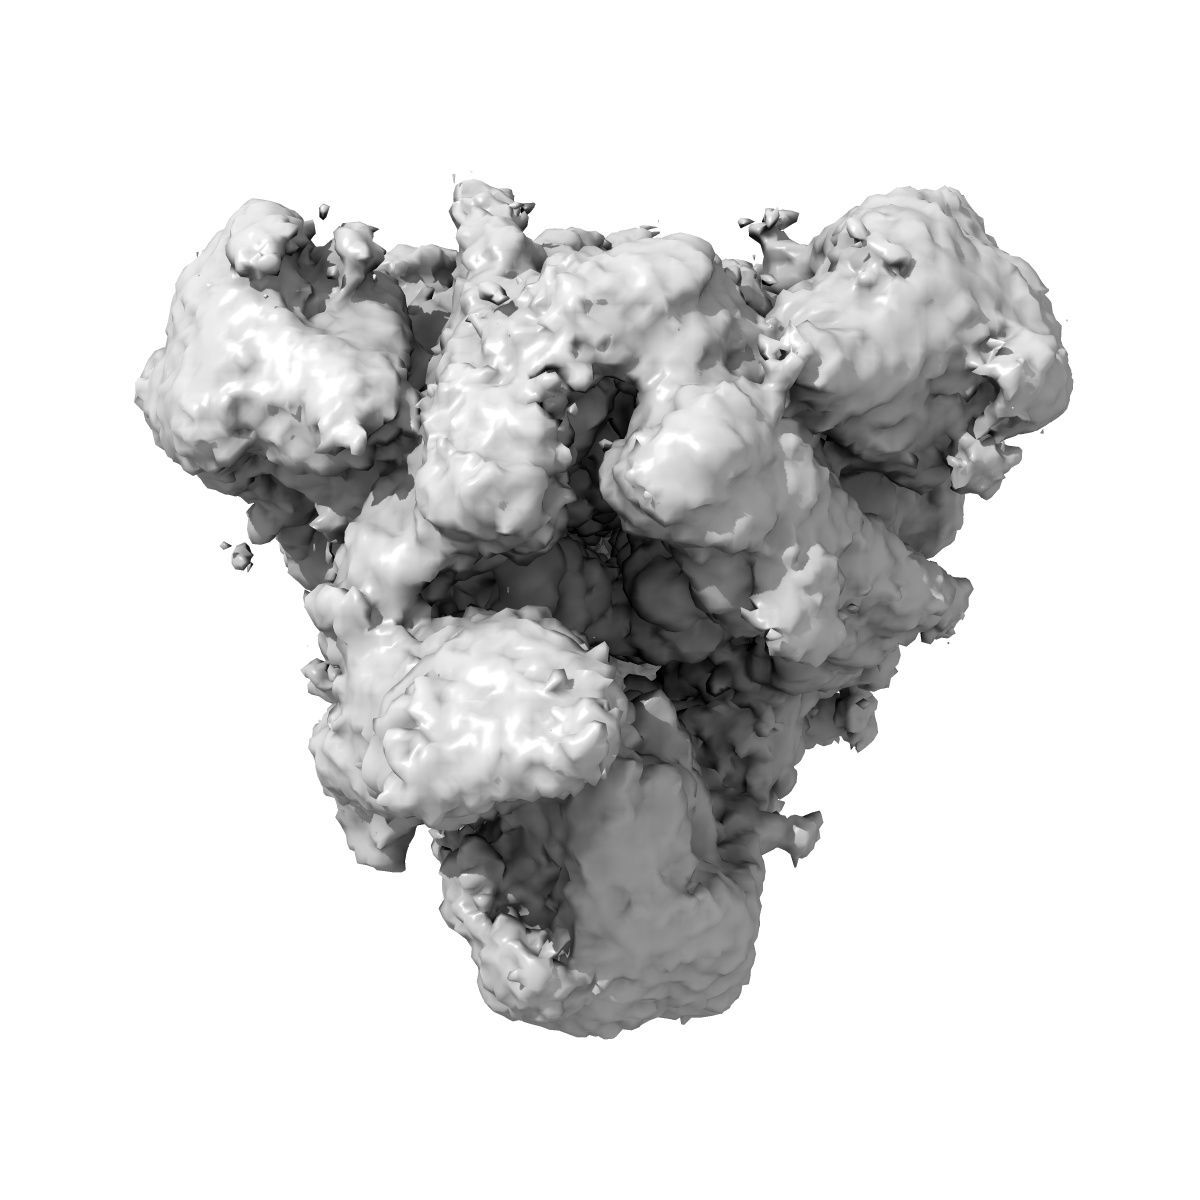

SARS-CoV-2 Spike protein Beta Variant at 4C structural flexibility / heterogeneity analyses

Sample: SARS-CoV-2 Spike protein Beta Variant at 4C